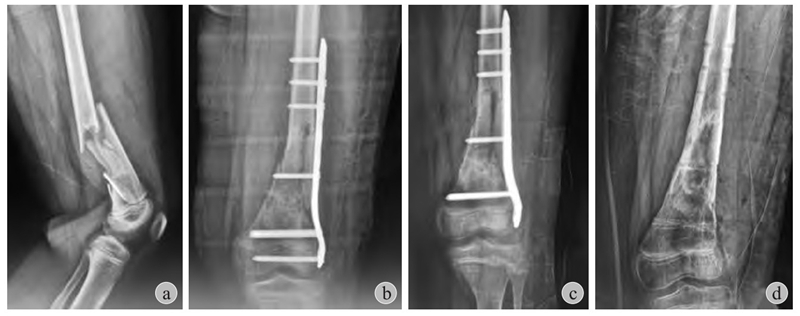

图2 患儿,男,11岁

a:右胫骨远端骨骺骨折(Salter-Harris Ⅱ型)合并腓骨远端骨折;b:闭合复位,胫骨远端6枚克氏针贯通骺板固定;c:术后4个月见右小腿远端红肿,流脓;d:愈合后出现胫骨远端骺板早闭(星号)+局部皮质骨坏死(箭头)+慢性骨髓炎形成